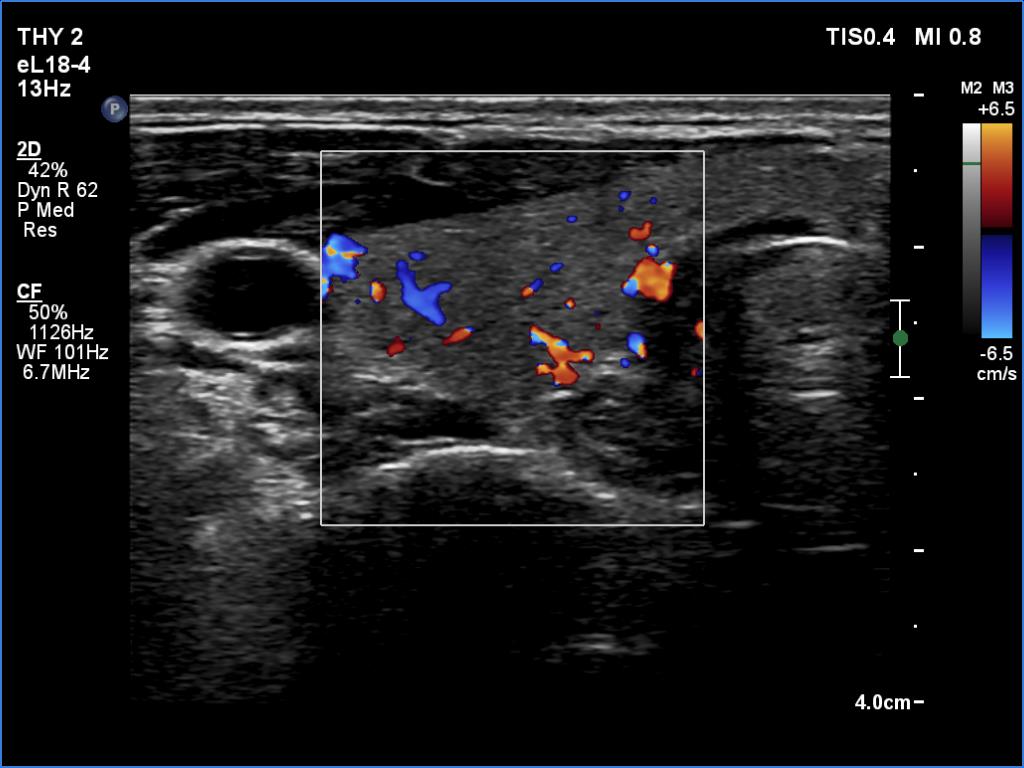

Ultrasound. Both lobes were echonormal and intact. The vascularity was average.